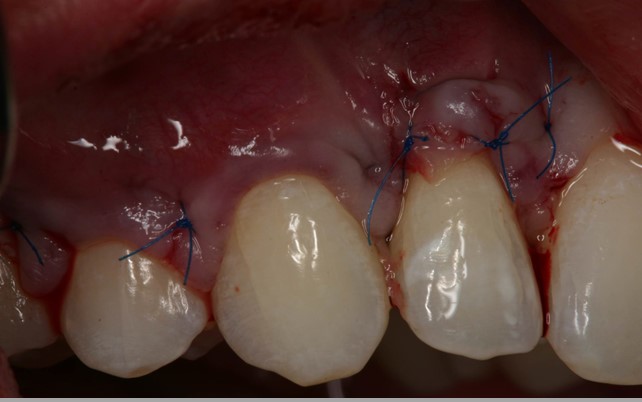

04/06 - The flap is repositioned in coronal direction to cover the root surfaces and the mucoderm® matrix completely.Multiple gingival recessions treated with the modified coronally advanced flap in conjunction with mucoderm® - Prof. Dr. Dr. A. Kasaj

02/06 - Flap preparation according to the modified coronally advanced flap technique (Zucchelli & De Sanctis J Periodontol. 2000). Sulcular incision from tooth 11 to 15 and elevation of a splitthickness flap.Multiple gingival recessions treated with the modified coronally advanced flap in conjunction with mucoderm® - Prof. Dr. Dr. A. Kasaj